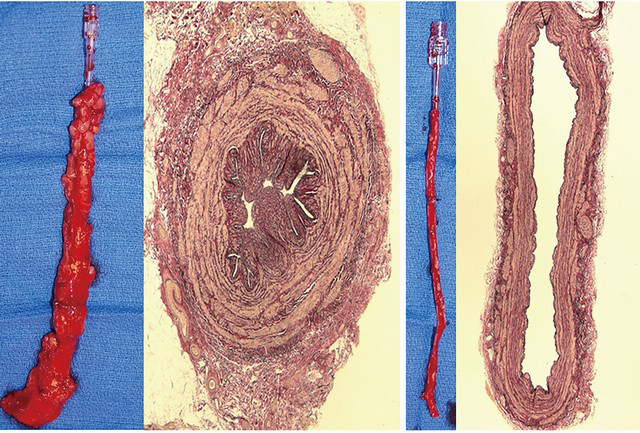

Na recente edição do Brazilian Journal of Cardiovascular Surgery, Domingos Souza et al. descreveram o passo-a-passo da técnica “no-touch” para…

A complexidade da técnica aplicada em muitos procedimentos cirúrgicos, principalmente na área cardíaca, constitui um dos maiores desafios para o…